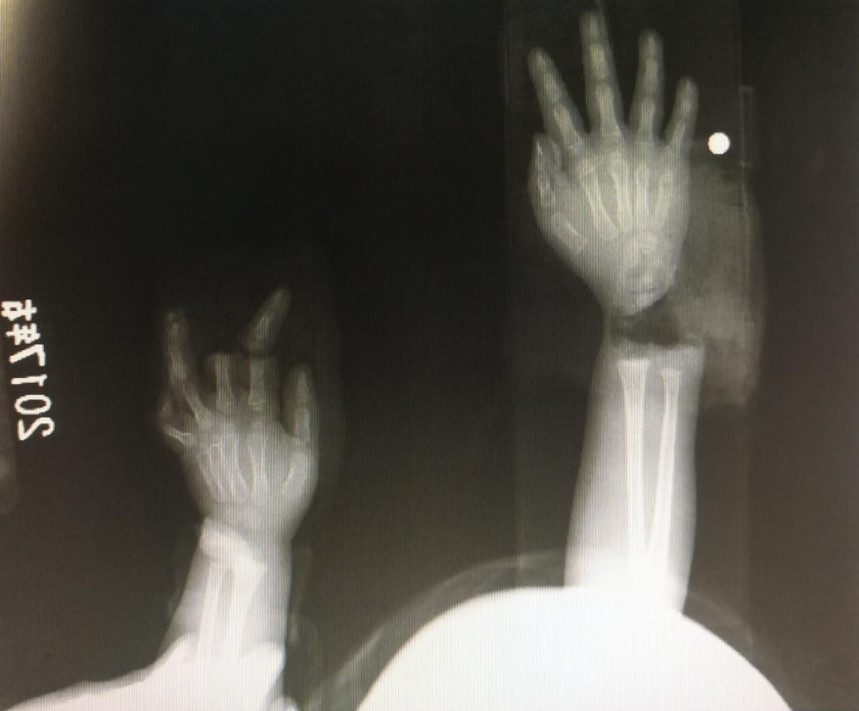

“急診在哪,急診在哪”,伴隨著一聲聲急促的問詢,一位年輕女士抱著渾身是血的小孩疾步前往急診室,懷里的小孩在疲憊與疼痛的交織下,時睡時醒。鑒于小孩的情況,急診醫(yī)生迅速安排給小孩拍了X光片,影像片結(jié)果顯示小孩左手手腕完全離斷,右手中、食指離斷,距離事發(fā)時間已經(jīng)3個多小時,需盡快安排手術(shù)。

經(jīng)過長達5個多小時的手術(shù),小宇(化名)終于被送出了手術(shù)室,離斷的手腕和手指均已完成再植,但關于斷指的存活與否還需要經(jīng)過一個十天的觀察期。小宇的主治醫(yī)生是長沙年輪骨科醫(yī)院手足外科馬思成醫(yī)生,據(jù)馬醫(yī)生介紹,小宇受傷情況比較嚴重,失血過多,而且兩個手都存在完全離斷的情況,手術(shù)時安排了兩組醫(yī)生同時進行,整個手術(shù)過程比較順利,目前小宇還處于觀察期。